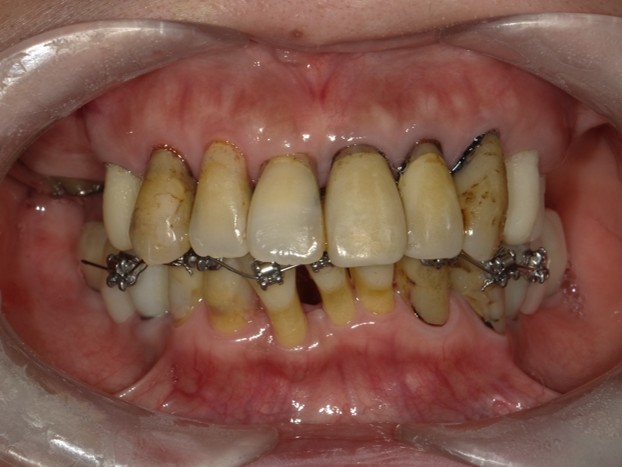

外科矯正治療・インプラント治療・セラミック治療の症例紹介(三隅歯科クリニック)

| 主訴 | 50代男性 右上の歯と歯茎が痛い。どこで噛んでいいのか分からないので夜も眠れない |

| 治療内容 | 外科矯正治療・インプラント治療・セラミック治療を行いました。 |

| 治療費 | 4,500,000円(税込み) |

| 治療期間 | 4年(矯正治療期間 3年) |

| 治療回数 | 60回 |

| 想定されたリスク | 顎骨の変形があったので、全身麻酔下による外科処置が必要になり、身体的、精神的負担が増す可能性がありました。 清掃状況によっては矯正中にむし歯が発生するリスクがありました。 |